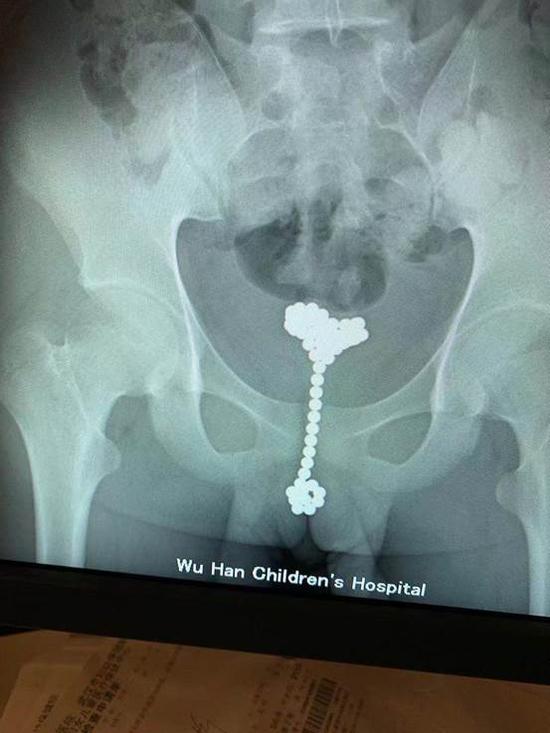

无独有偶,就在上周,还有一名13岁的少年李辰(化名),因为“肚子痛”就诊,被收治进了普外科。医生本以为是吞了异物,但该科急诊医生李欢一看片子,发现有一串金属物竟在膀胱内。

李辰不好意思地承认,自己是为了“探索人体”,一时好奇才将珠子塞进去的,已经过去两个多月了。李辰随后被转到泌尿外科,王军主任手术取出了31颗巴克球。